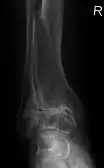

Diagnosis is made with reasonable certainty based on history and clinical examination.[51][52] X-rays may confirm the diagnosis. The typical changes seen on X-ray include: joint space narrowing, subchondral sclerosis (increased bone formation around the joint), subchondral cyst formation, and osteophytes.[53] Plain films may not correlate with the findings on physical examination or with the degree of pain.[54]

MRI of osteoarthritis in the knee, with characteristic narrowing of the joint space